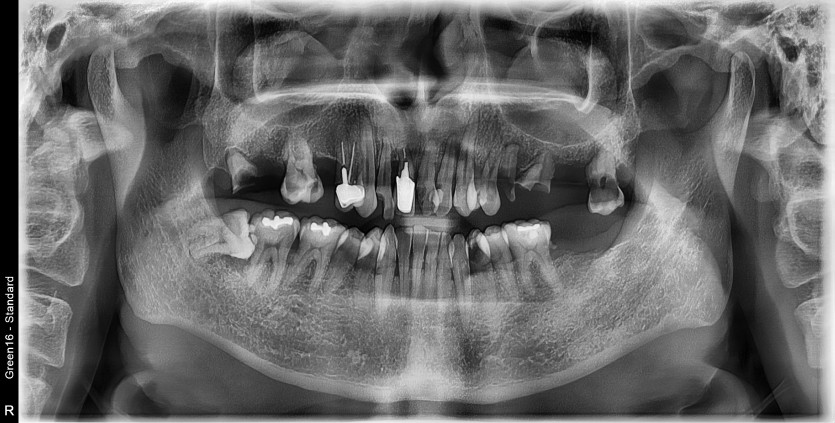

만 45세 상악 전체 임플란트 증례

상악 전체 임플란트 증례입니다.

10개의 임플란트로 완성하였습니다.